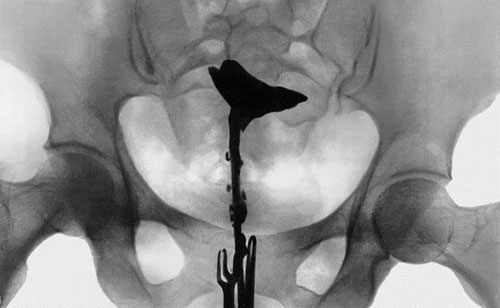

Гистеросальпингография маточных труб (метросальпингография) представляет собой рентгенологическое исследование особенностей полости матки и проходимости маточных труб. Это информативный способ изучения строения и функции репродуктивной системы женщины. Кроме этого метода существуют:

Процедура гистеросальпингографии проводится в специальном кабинете, оборудованном рентген-аппаратом.

1. Женщина ложится на гинекологическое кресло. Во влагалище вводятся гинекологические зеркала для получения доступа к шейке матки.

2. Влагалище и шейка матки обрабатываются антисептиком. В цервикальный канал устанавливается канюля.

3. Зеркала извлекаются, и женщина ложится горизонтально.

4. По специальной трубке небольшими порциями в полость матки вводится стерильное контрастное вещество, содержащее йод (урографин, венографин, уротраст и др.).

5. По мере заполнения им матки и маточных труб производится серия рентгенологических снимков. Длительность исследования зависит от индивидуальных особенностей женщины.

Результаты гистеросальпингографии позволяют лечащему врачу сделать вывод об особенностях строения полости матки и маточных труб.

• Исследование может показать частичную или полную непроходимость маточных труб. В случае полной непроходимости контрастное вещество не выявляется в брюшной полости.

• Колбообразное расширение маточной трубы может иметь место при гидросальпинксе.

• Неровность контура полости матки и дефект ее наполнения свидетельствует о наличии полипа эндометрия или субмукозной миомы матки.